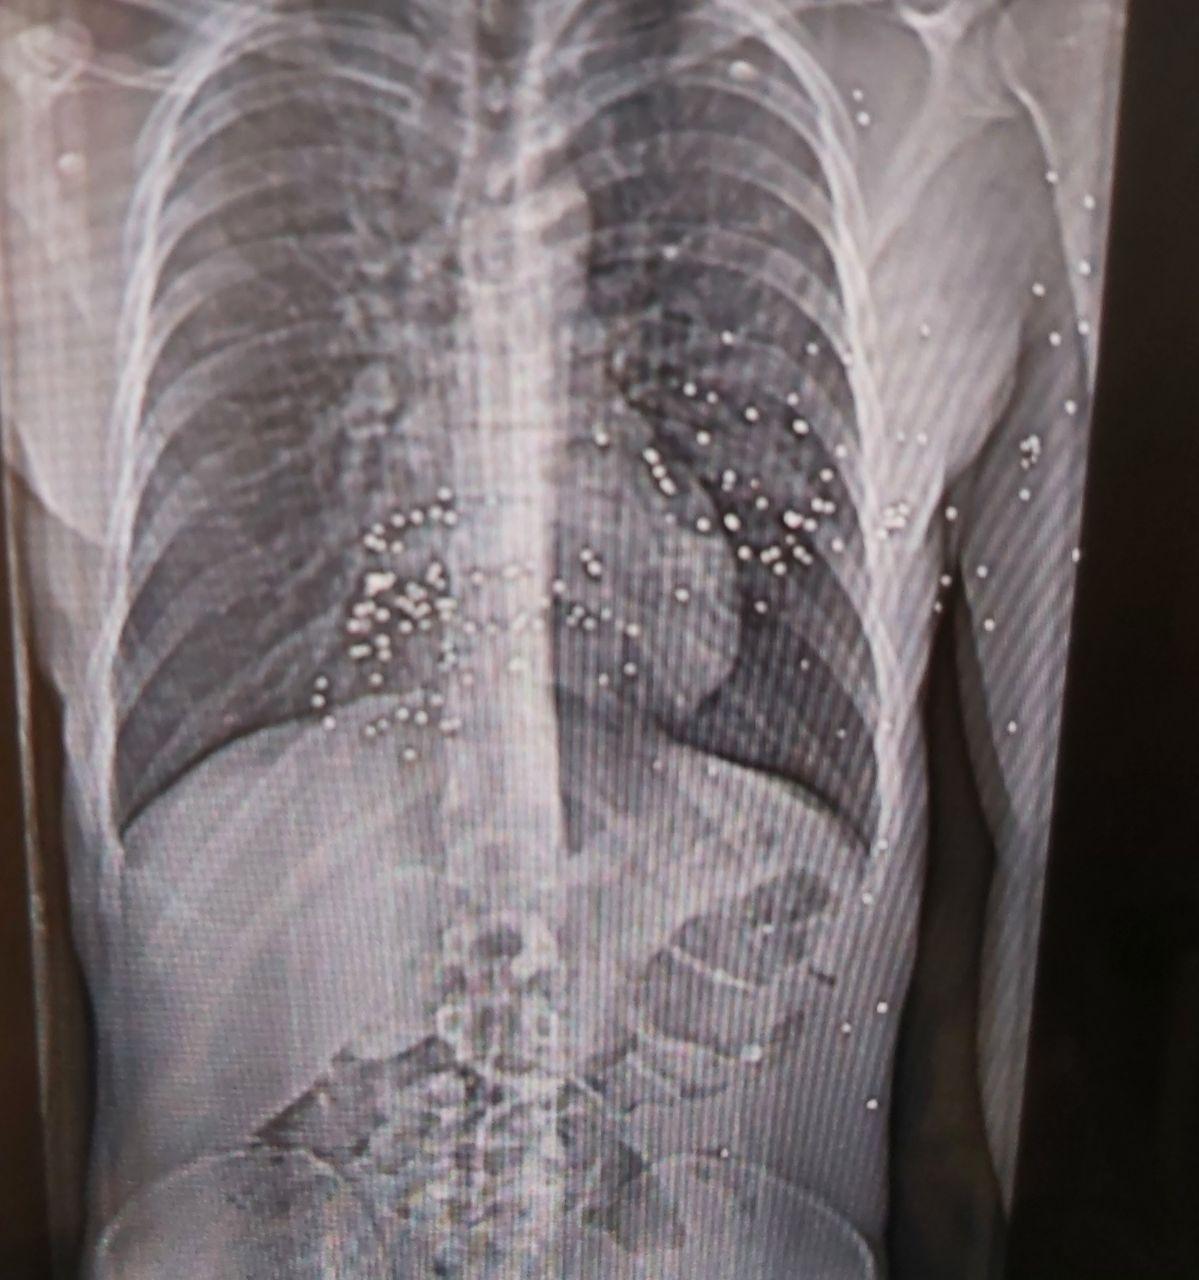

نیویورکر نوشت اعضای کادر درمان در هفتههای اخیر خود به مستندسازی شواهد حملات حکومت به مردم ایران پرداختهاند و برخی مدارک از جمله تصاویر سیتیاسکن مجروحان را در اختیار این مجله قرار دادهاند.

نرگس این وضعیت را «جهنمی» توصیف کرد: نوجوانی ۱۴ ساله با پاهایی نحیف که با ساچمههای فلزی هدف قرار گرفته بود؛ مردی با حفرهای به اندازه توپ تنیس در ساق پا که او در بخیه زدن آن کمک کرد.